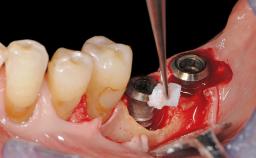

Peri-Implant Tissue Health

Maintenance of healthy peri-implant soft tissue as well as supporting peri-implant bone is an essential part of long-term success of implant therapy. An accurate maintenance protocol of peri-implant tissue health may prevent biological complications such as peri-implantitis. After the delivery of the prosthesis, patients should be followed up and clinical and radiological examinations should be performed on a regular basis to detect any etiological factors that may lead to such complications. This topic discusses properties of healthy and pathological conditions of peri-implant tissue, clinical and radiological examination methods of peri-implant tissue, as well as protocols for maintaining peri-implant tissue health.